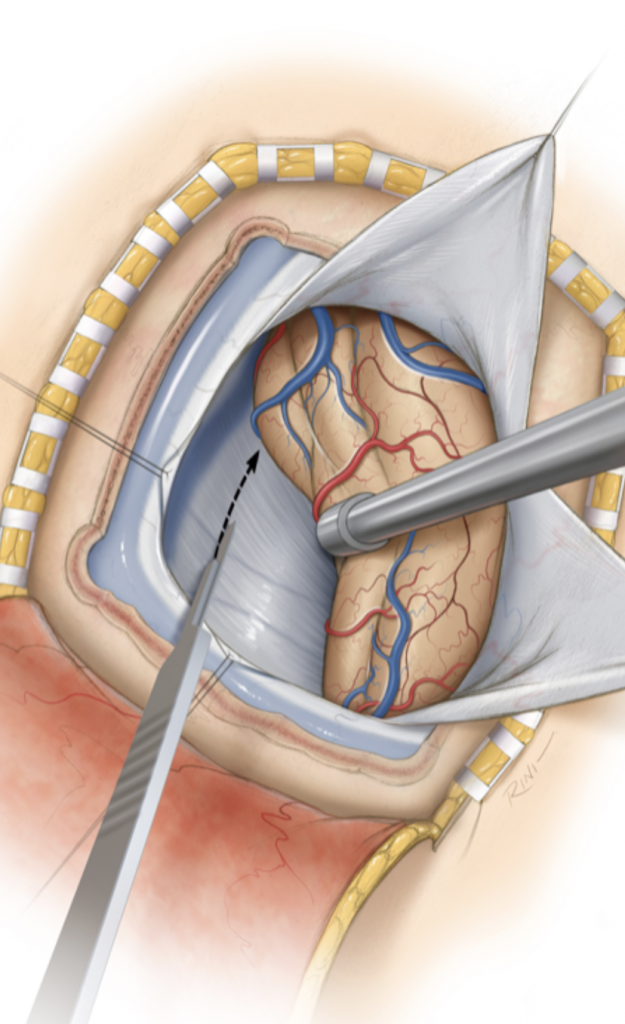

Figure 2: Images demonstrating the right occipital / transtentorial operative approach.

The traditional surgical approach to this region is the midline supracerebellar approach, performed with the patient in the seated position. We chose instead the right occipital / transtentorial approach. The major advantages of this alternative approach are (1) it is much easier technically for the surgeon, and (2) the risk of a serious air embolus is much lower. The major risk of surgery in the pineal region is injury to one of the large deep veins, which can result in a serious venous infarct.